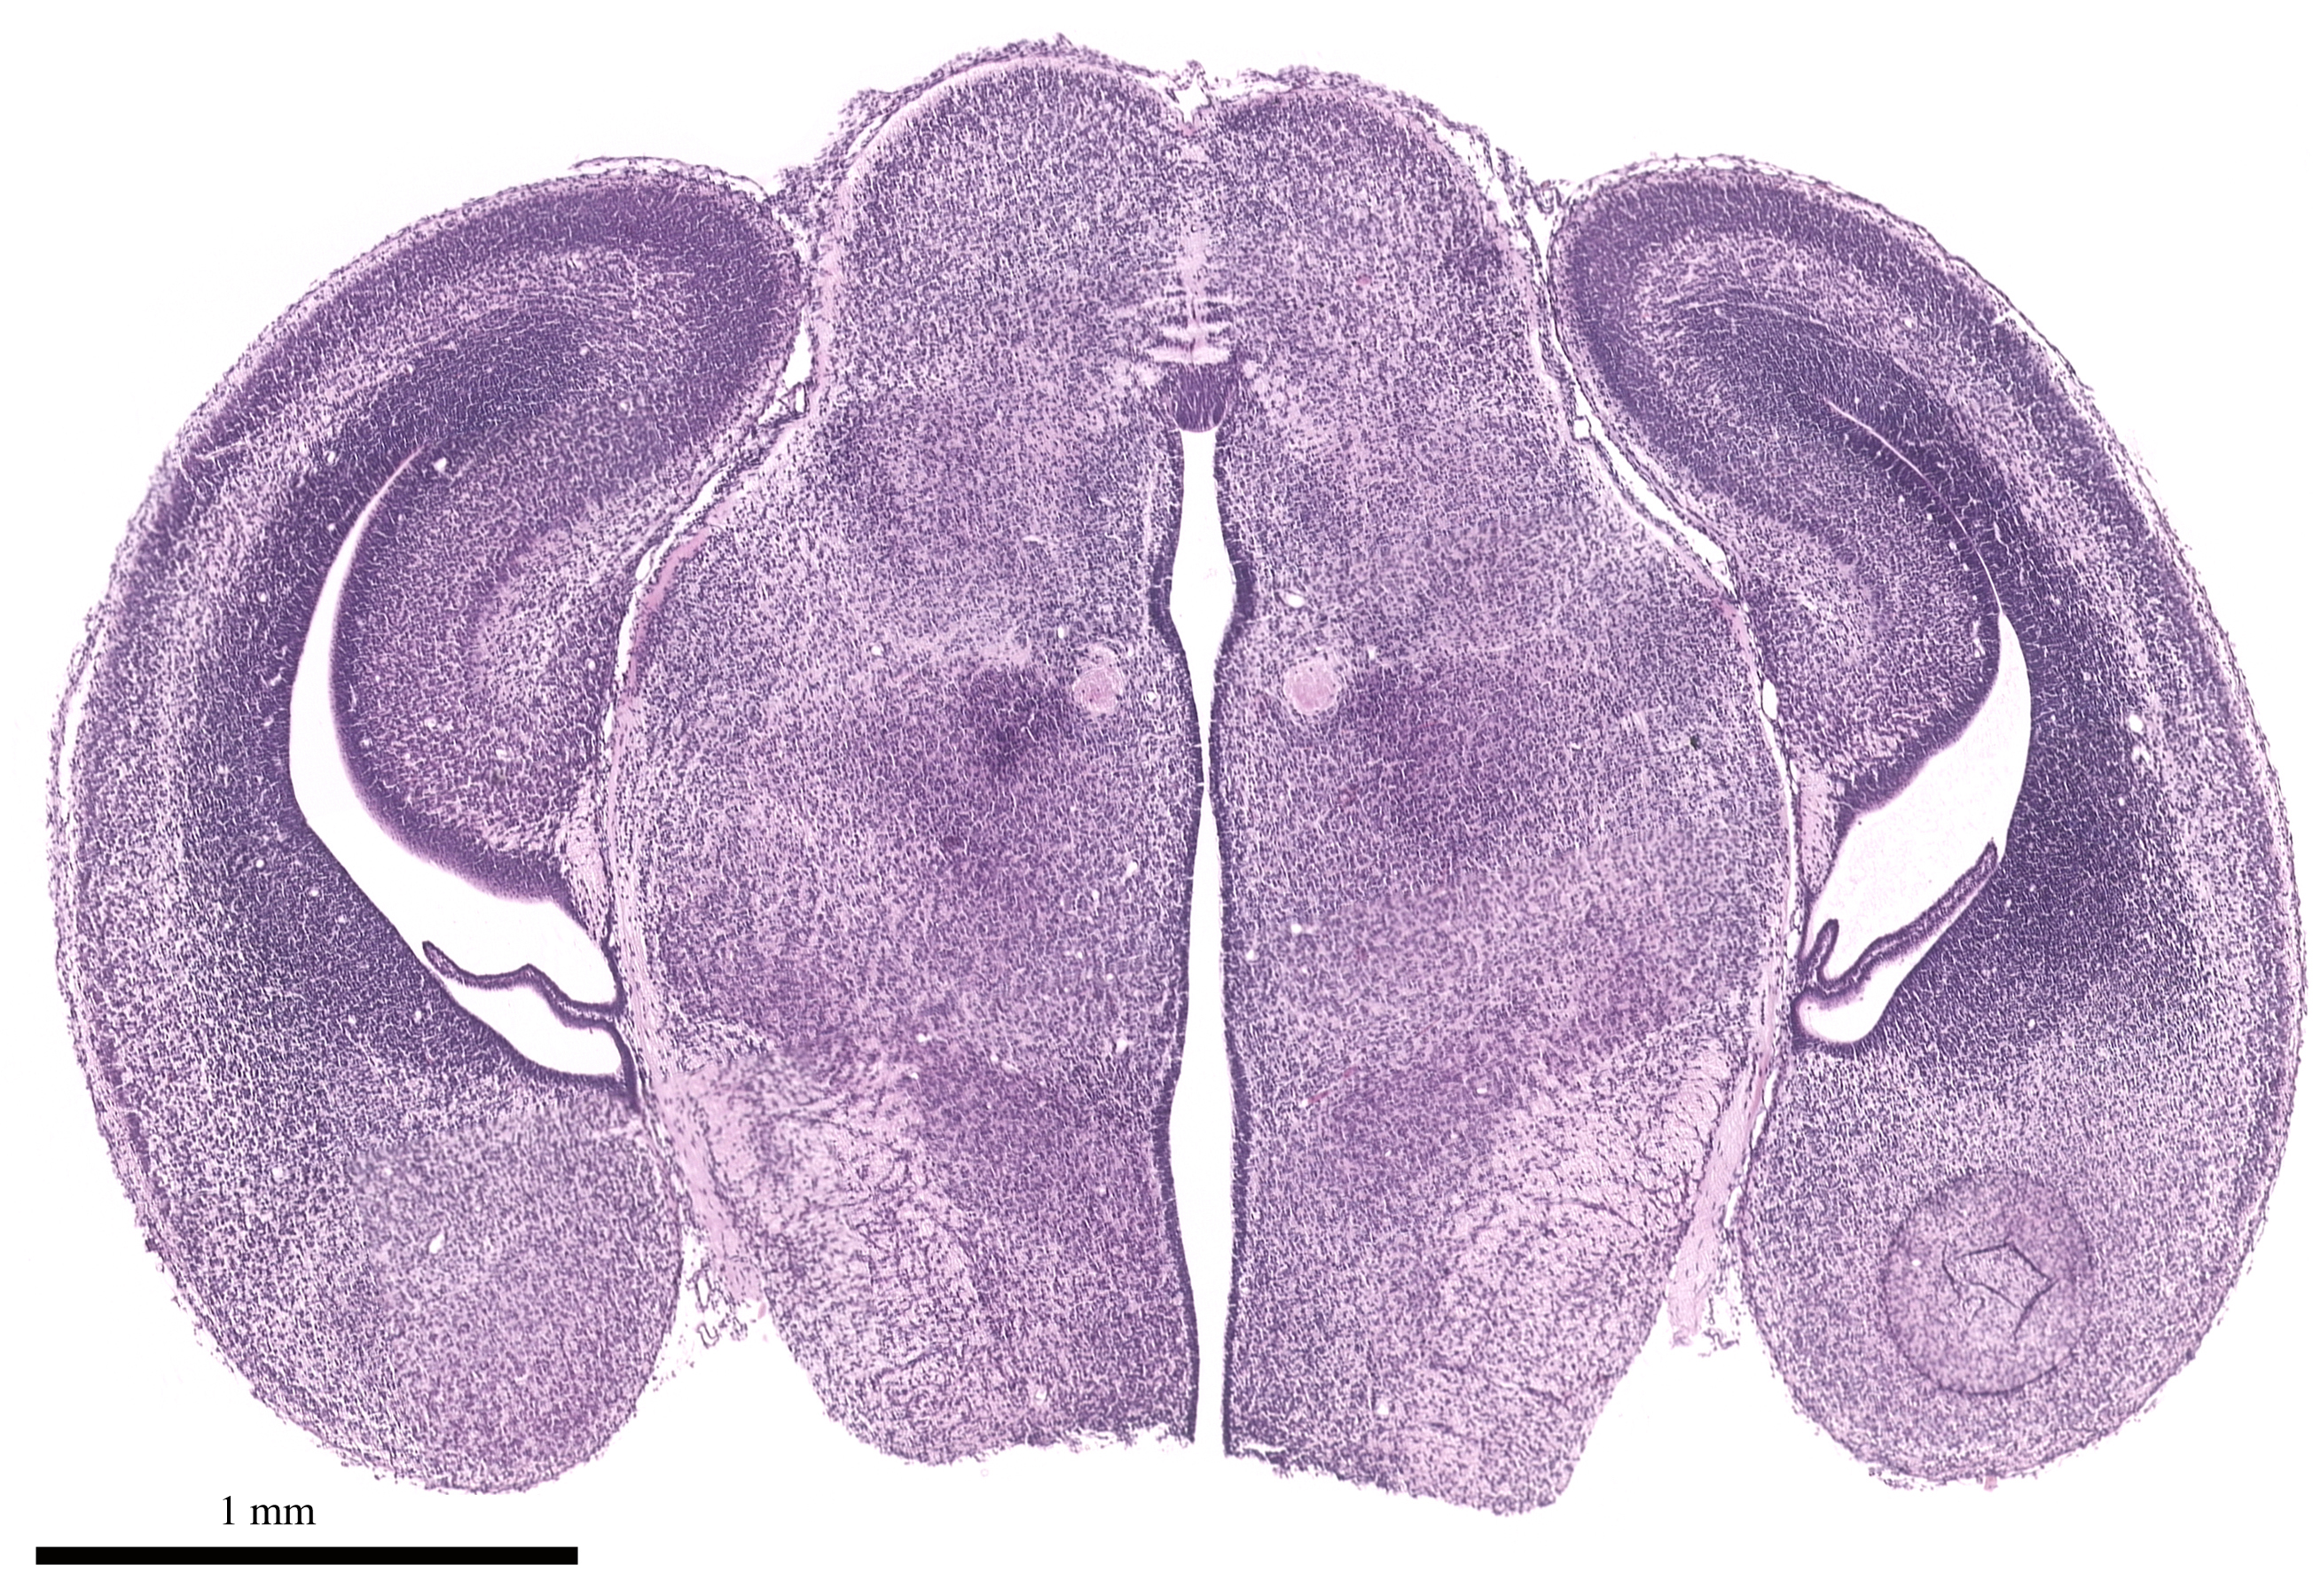

| DG |

Dentate gyrus (fascia dentata) |

155,

| HI |

Hippocampus |

121,